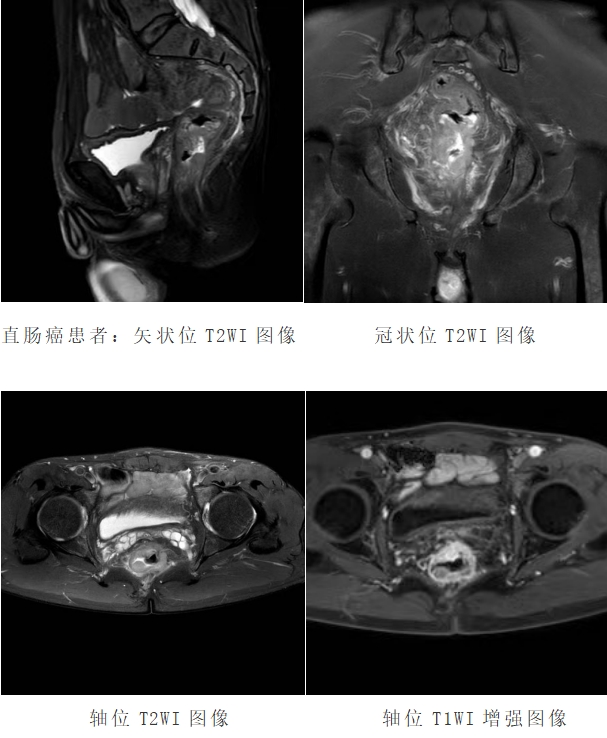

直肠磁共振检查是根据直肠的解剖特点,采用高分辨率2D或3D 磁共振成像序列,并合理利用脂肪抑制技术,通过选择多种成像方位,形成不同组织对比度的直肠MRI图像,以突显病变特征,从而用于诊断直肠疾病的磁共振检查技术。

直肠磁共振具有较高的软组织分辨率、无辐射和多方位成像的优点,可清楚显示肿瘤与周围结构的关系。在 T2WI 图像上,可清晰显示直肠壁的三层结构,对于直肠癌的临床分期具有重要作用,从而为患者个体化的治疗和预后评估提供有力支持。